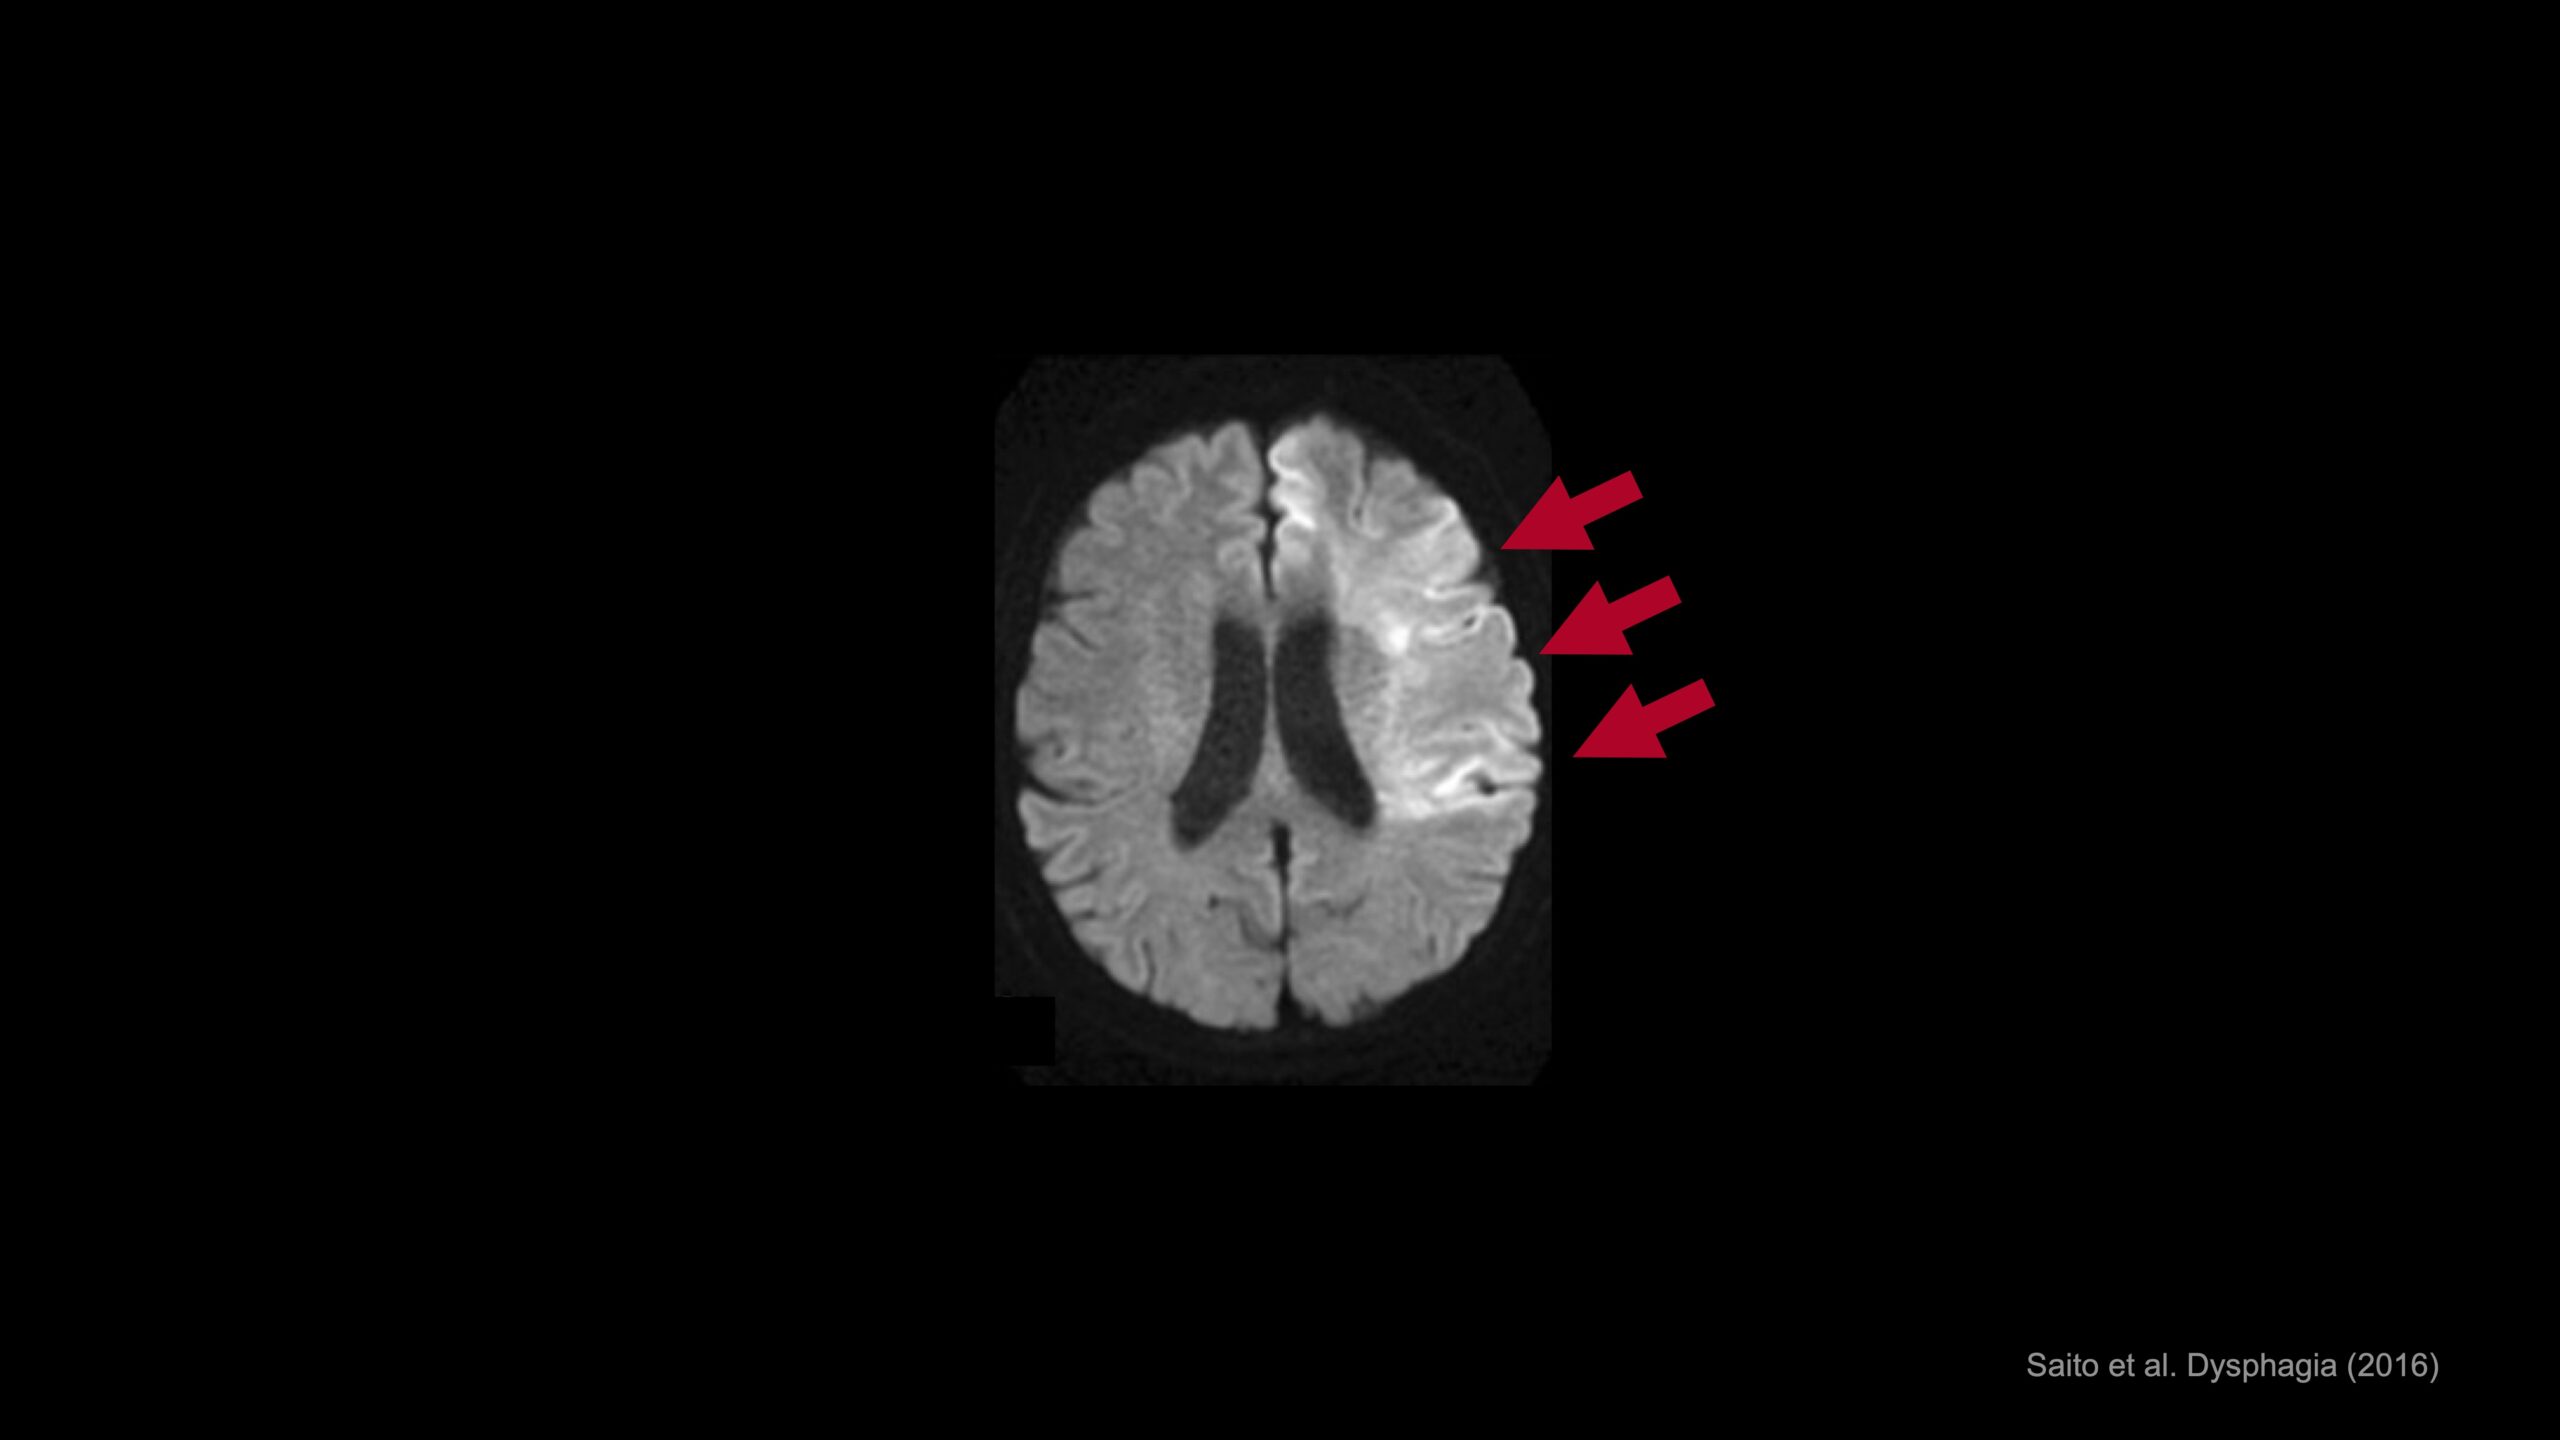

こちらは、重度症例のMRI画像です。

麻痺している右手を動かそうとしても、運動の生成に必要な運動野には活動が見られません。

しかし、1日40分の訓練をたった10日間続けることで、運動野の活動が新たに出現することが分かりました。

さらに、積み木を掴んだ後、握り込んでしまって離せなかった右手が、2週間後には積み木を掴んだり、離したりすることができるようになりました。

臨床研究の結果、既存治療では回復が難しかった重度症例においても、治療効果は実に74%という成績を収めました。

このように、脳波計で残存した脳活動を計測し、ロボットで体の動きをアシストすることで、代償経路が構築され、麻痺した手を回復できることを、私たちは世界に先駆けて示したのです。